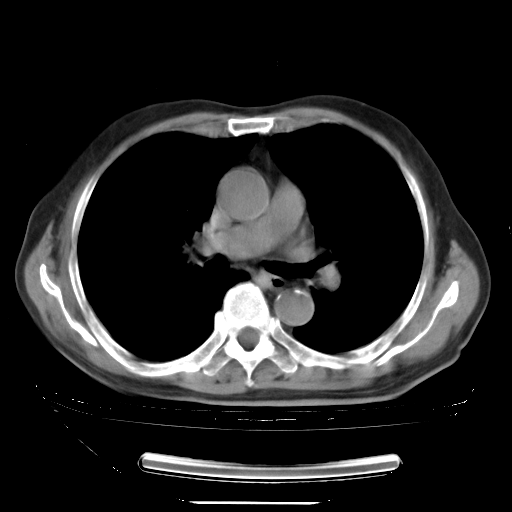

今天复查肺部CT,发现双肺广泛磨玻璃样改变。所以我把3月19日和5月9日相隔50天的肺部CT上传。请大家会诊。

5月9日肺部CT(在4月27日齐鲁医院肺部CT描述部分肺组织磨玻璃样改变,12天后肺组织广泛磨玻璃样改变)

2009年5月9日肺部CT

大致读了系列胸部CT:纵隔窗无明显异常,肺窗:从4、27至今:主要是双肺中下野外带可见毛玻璃样改变,目前处于急性肺泡炎阶段,至于原因考虑1、结替组织或胶原血管性疾病所致?2、恶性疾病如恶组在肺部所致的表现或细支气管肺泡癌?3、药物或其它原因如肺蛋白沉着症所致肺泡炎目前不太可能?总之,明天就去请我院的呼吸科、感染科、血液科和临免专家会诊哈。